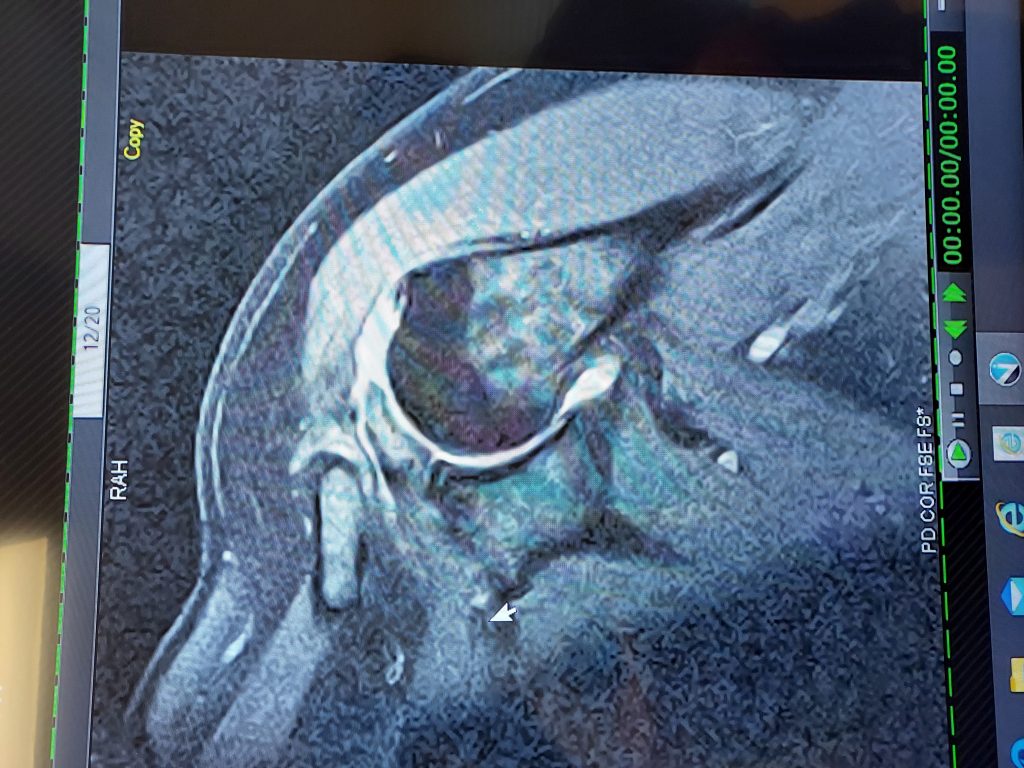

I had arthroscopy surgery on 3/1/23 performed by a surgeon from a different group. He did an amazing job repairing my torn rotator cuff, but unfortunately it did not hold probably due to me going back to lifting weights. I decided to seek out Dr Ryan Simovitch at HSS Florida as he performed extensive rotator cuff and biceps surgery on me in 2018. Dr. Simovitch repaired my rotator cuff, which was torn worse that my 1st surgery. My biceps, labrum, and bursa were also damaged. To say the care and concern shown to my by Dr Simovitch, his his team, and the HSS Florida staff was exceptional would be an understatement. Dr. Simovitch is by far the best shoulder surgeon in the country - maybe even the world in my opinion! He did an amazing job. I've had 33 surgeries and many skilled surgeons, but Dr Simovitch is in a class all by himself. Thank you so much. A debt of gratitude and appreciation.